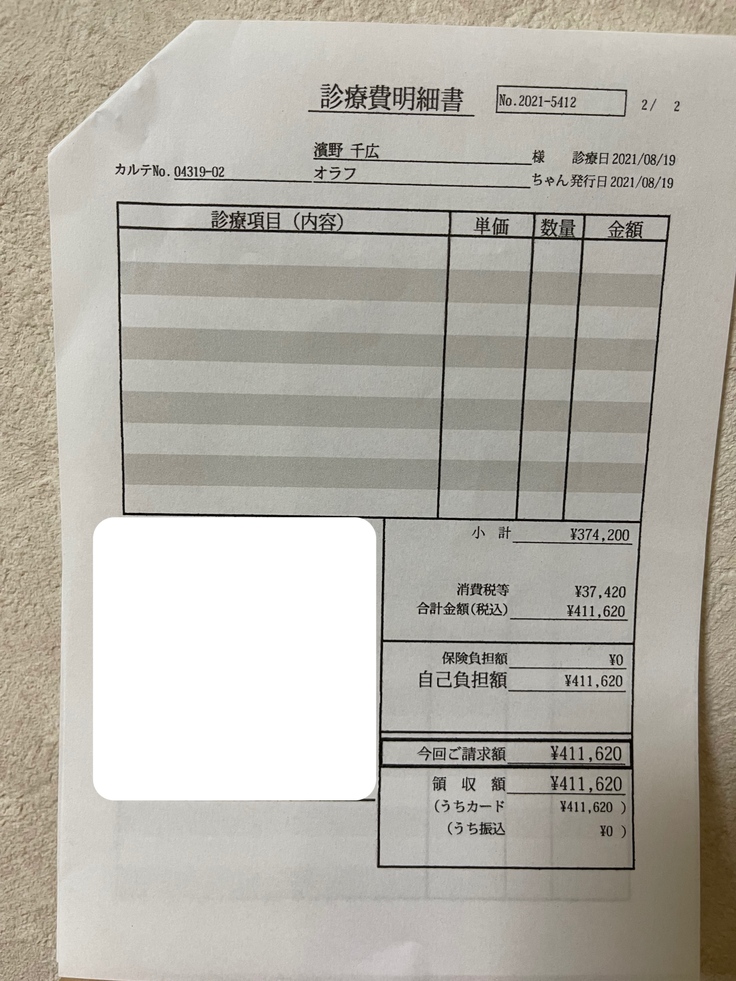

★薬代 8/3~8/26 12,375円(450mg)×24日

8/27~10/3 13,750円(500mg)×38日

10/4~10/25 15,125円(550mg)×22日

84日間の合計1,152,250円です。

★検査費等 85,382円

これまでのFIP治療費は1,237,632円です。

検査費と薬代です。